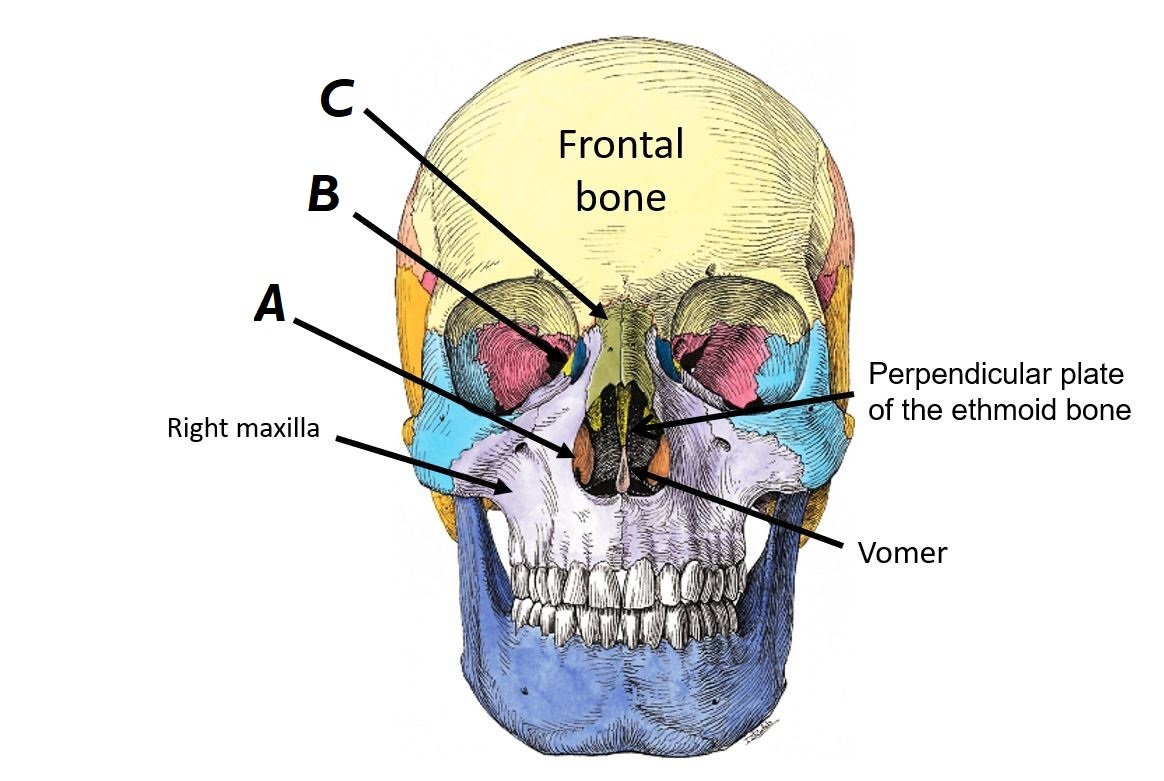

Name bones A, B and C

A - Right inferior nasal concha

B - Ethmoid bone

C - Right nasal bone

Name bones A to D

A - Right maxilla

B - Vomer

C - Ethmoid bone (perpendicular plate)

D - Frontal bone